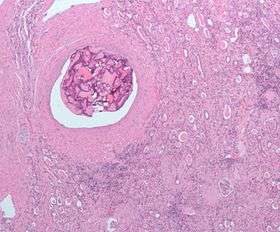

| Micrograph of the most common type of renal cell carcinoma (clear cell)—on right of the image; non-tumour kidney is on the left of the image. Nephrectomy specimen. H&E stain | |

Histopathology

The gross and microscopic appearance of renal cell carcinomas is highly variable. The renal cell carcinoma may present reddened areas where blood vessels have bled, and cysts containing watery fluids.[54] The body of the tumour shows large blood vessels that have walls composed of cancerous cells. Gross examination often shows a yellowish, multilobulated tumor in the renal cortex, which frequently contains zones of necrosis, haemorrhage and scarring. In a microscopic context, there are four major histologic subtypes of renal cell cancer: clear cell (conventional RCC, 75%), papillary (15%), chromophobic (5%), and collecting duct (2%). Sarcomatoid changes (morphology and patterns of IHC that mimic sarcoma, spindle cells) can be observed within any RCC subtype and are associated with more aggressive clinical course and worse prognosis. Under light microscopy, these tumour cells can exhibit papillae, tubules or nests, and are quite large, atypical, and polygonal.

The recommended histologic grading schema for RCC is the Fuhrman system (1982), which is an assessment based on the microscopic morphology of a neoplasm with haematoxylin and eosin (H&E staining). This system categorises renal cell carcinoma with grades 1, 2, 3, 4 based on nuclear characteristics. The details of the Fuhrman grading system for RCC are shown below:[58]